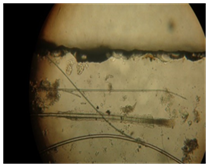

Grossly T. mentagrophytes colonies were identified by having the colony characteristics of flat powdery to floccose or granular appearance, that are cream-colored to yellowish-buffed.14 Some strains produced a lavender-tinged surface.15 The colonies were frequently somewhat star-shaped and sometimes yellow or dark brown.14 In microscopic examination, colonies were subjected to Lactophenol cotton-blue staining (used one drop of Lactofenol cotton blue) and these were microscopically examined. The most consistent feature of T. mentagrophytes was identified as abundance of microconidia arranged in grape-like structures or alongside the hyphae. Spiral or coiled hyphae were frequently present.14

Figure 9 Microscopic structure.